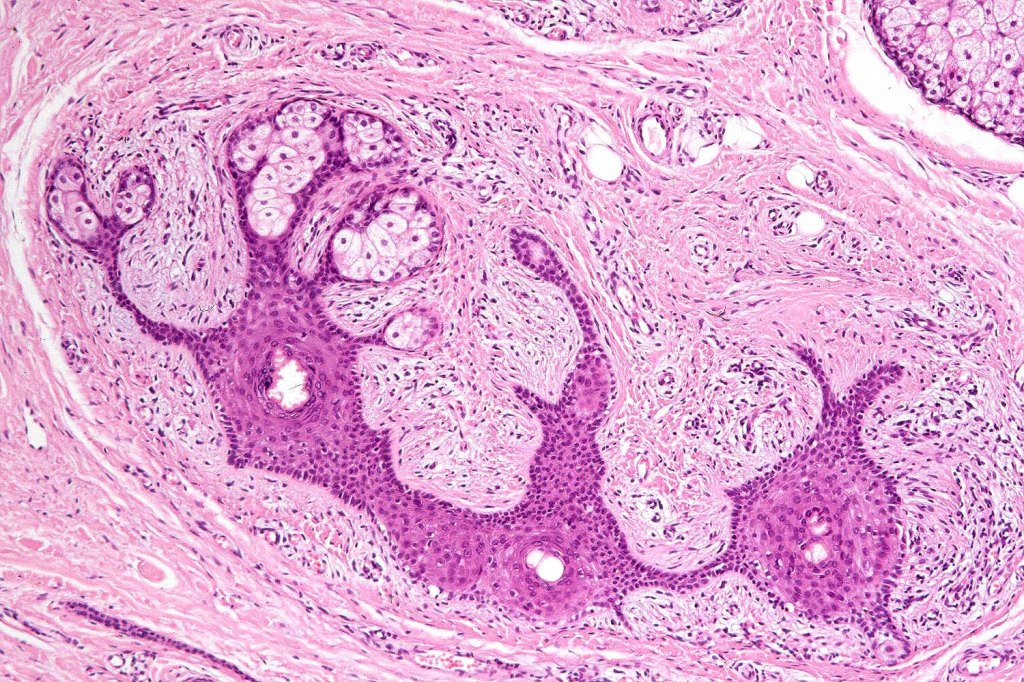

•Circumscribed dermal nodule with a characteristic silhouette

•An infundibular cyst is surrounded by laminated dermal collagen, elastic fibers, blood vessels, adipocytes & spindle cells separated from the adjacent dermis by a retraction artifact

•The cyst contains keratinous debris, and its wall shows conspicuous sebaceous & sometimes hair follicular elements are also evident